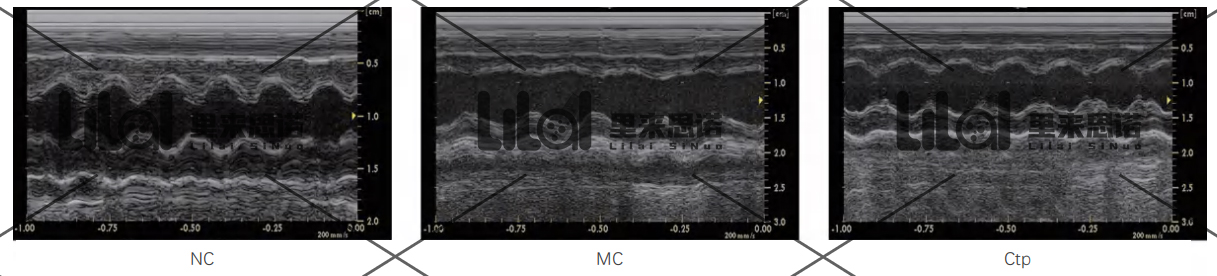

心功能檢測:實驗結束后進行心臟超聲,檢測各組大鼠的心功能。結果發現:與NC組相比,MC組大鼠左室射血分數(LVEF)和左室短軸縮短率

(LVFS)顯著降低;而Ctp能顯著提高心衰大鼠LVEF和LVFS,改善心衰大鼠心功能(p<0.01)。